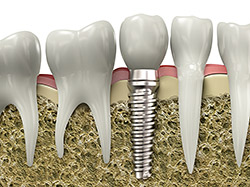

If you have missing teeth it is

crucial to replace them. Without all your teeth, chewing and eating can

destabilize your bite and cause you discomfort. When teeth are missing

your mouth can shift and even cause your face to look older. Implants are

a great way to replace your missing teeth and if properly maintained can last a

lifetime!

An implant is a new tooth made of metal and porcelain that looks just like your natural tooth. It’s composed of two main parts: One part is the titanium implant body that takes the place of the missing root and the second part is the tooth-colored crown that is cemented on top of the implant. With implant treatment you can smile confidently knowing no one will ever suspect you have a replacement tooth.

In addition to tooth replacement, implants may be used to anchor dentures, especially lower dentures that tend to shift when you talk or chew. For patients with removable partial dentures, implants can replace missing teeth so you have a more natural-looking smile.